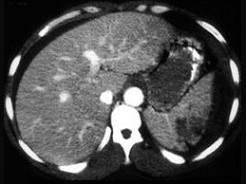

下列图像最佳诊断是 ( )A、脾破裂B、结肠破裂C、胰腺损伤D、小肠破裂E、肝破裂

问题 下列图像最佳诊断是 ( )

选项 A、脾破裂 B、结肠破裂 C、胰腺损伤 D、小肠破裂 E、肝破裂

答案 A